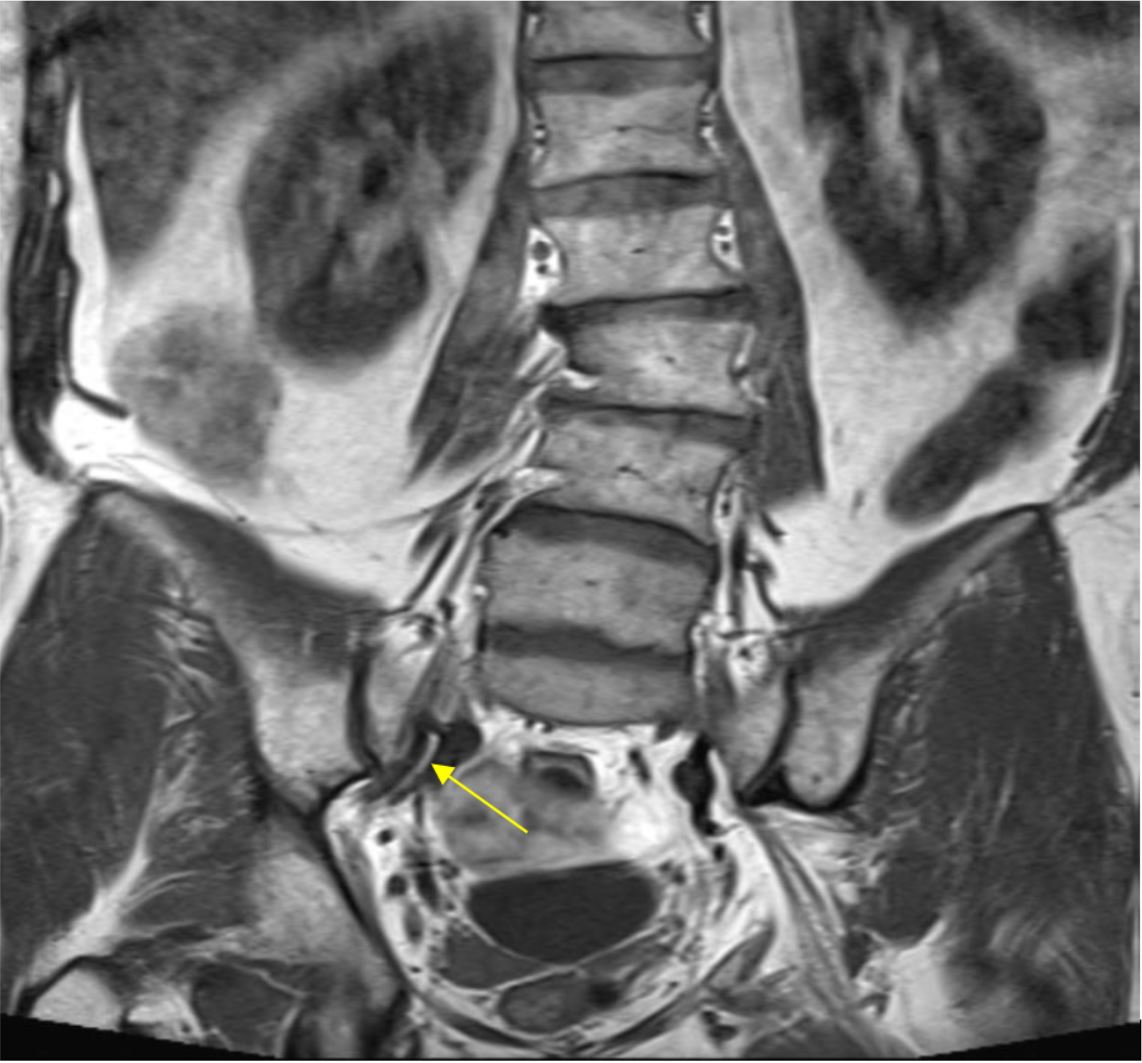

The insufficient capsular envelope around the joint (particularly being thin or deficient anteriorly) may explain the mechanism or pathway that inflammatory pain mediators can leak through onto the neural structures. This also likely accounts for the radicular leg pain (“sciatica”) commonly seen, especially in the distribution of the main L5 nerve, which lies 10-12mm anterior to the joint.

Yellow arrow pointing to L5 nerve